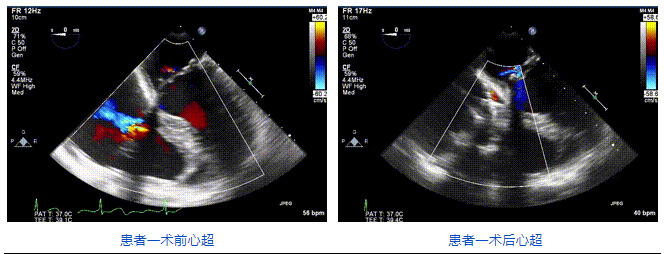

2021年12月24日,復(fù)旦大學(xué)附屬中山醫(yī)院葛均波院士團(tuán)隊(duì)成功應(yīng)用LuX-Valve Plus為一例極重度三尖瓣反流(TR)合并房顫、房缺的患者完成了經(jīng)血管三尖瓣置換術(shù),這是在前基礎(chǔ)上,本周完成的第三例經(jīng)血管三尖瓣置換手術(shù),葛均波院士、周達(dá)新教授等與心外科魏來教授、賴顥教授,心超室的潘翠珍教授、李偉教授及麻醉科的郭克芳教授共同完成了本周手術(shù),均獲得圓滿成功!患者術(shù)后超聲顯示無TR,臨床癥狀明顯改善。本周手術(shù)的成功也為L(zhǎng)uX-Valve Plus救治性臨床研究添上了濃墨重彩的一筆。

三例患者入院后,葛均波院士團(tuán)隊(duì)周達(dá)新教授、潘文志教授、張?jiān)床┦?、陳莎莎博士及心超室的潘翠珍教授、李偉教授?duì)患者的情況進(jìn)行詳細(xì)評(píng)估和討論,最終決定為三例患者選擇LuX-Valve Plus40mm、50mm和50mm型號(hào)的瓣膜進(jìn)行手術(shù)治療。手術(shù)后即刻拔除氣管插管,術(shù)后患者三尖瓣反流癥狀得到顯著改善,復(fù)查心超結(jié)果顯示人工三尖瓣瓣膜支架固定穩(wěn)定,瓣葉關(guān)閉形態(tài)未見異常,未見明顯反流。